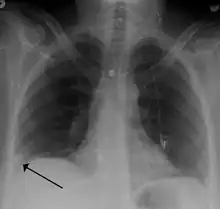

- Chest X-rays are often done on people with shortness of breath to help rule-out other causes, such as congestive heart failure and rib fracture. Chest X-rays in PE are rarely normal,[67] but usually lack signs that suggest the diagnosis of PE (for example, Westermark sign, Hampton's hump).

Pulmonary embolism (white arrow) that has been long-standing and has caused a lung infarction (black arrow) seen as a reverse halo sign.